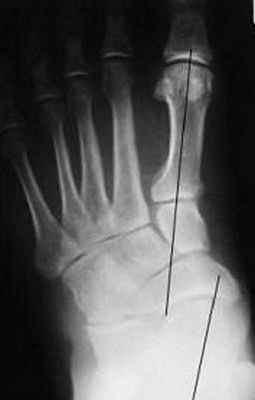

В первую очередь показано выполнение рентгенографии с нагрузкой в прямой и боковой проекции. При этом в прямой проекции выявляется неполное покрытие суставной поверхности головки таранной кости ладьевидной костью, увеличенный угол между таранной костью и первой плюсневой костью (угол Simmon), что встречается со 2 А стадии.

На боковых рентгенограммах определяется увеличенный таранно-плюсневый угол (угол Meary >4° свидетельствует о плоской стопе). Также снижается угол высоты пяточной кости (в норме 17-32°).

На 3-4 стадиях определяются признаки подтаранного артрита, на 4 стадии появляется картина подвывиха таранной кости в голеностопном суставе.